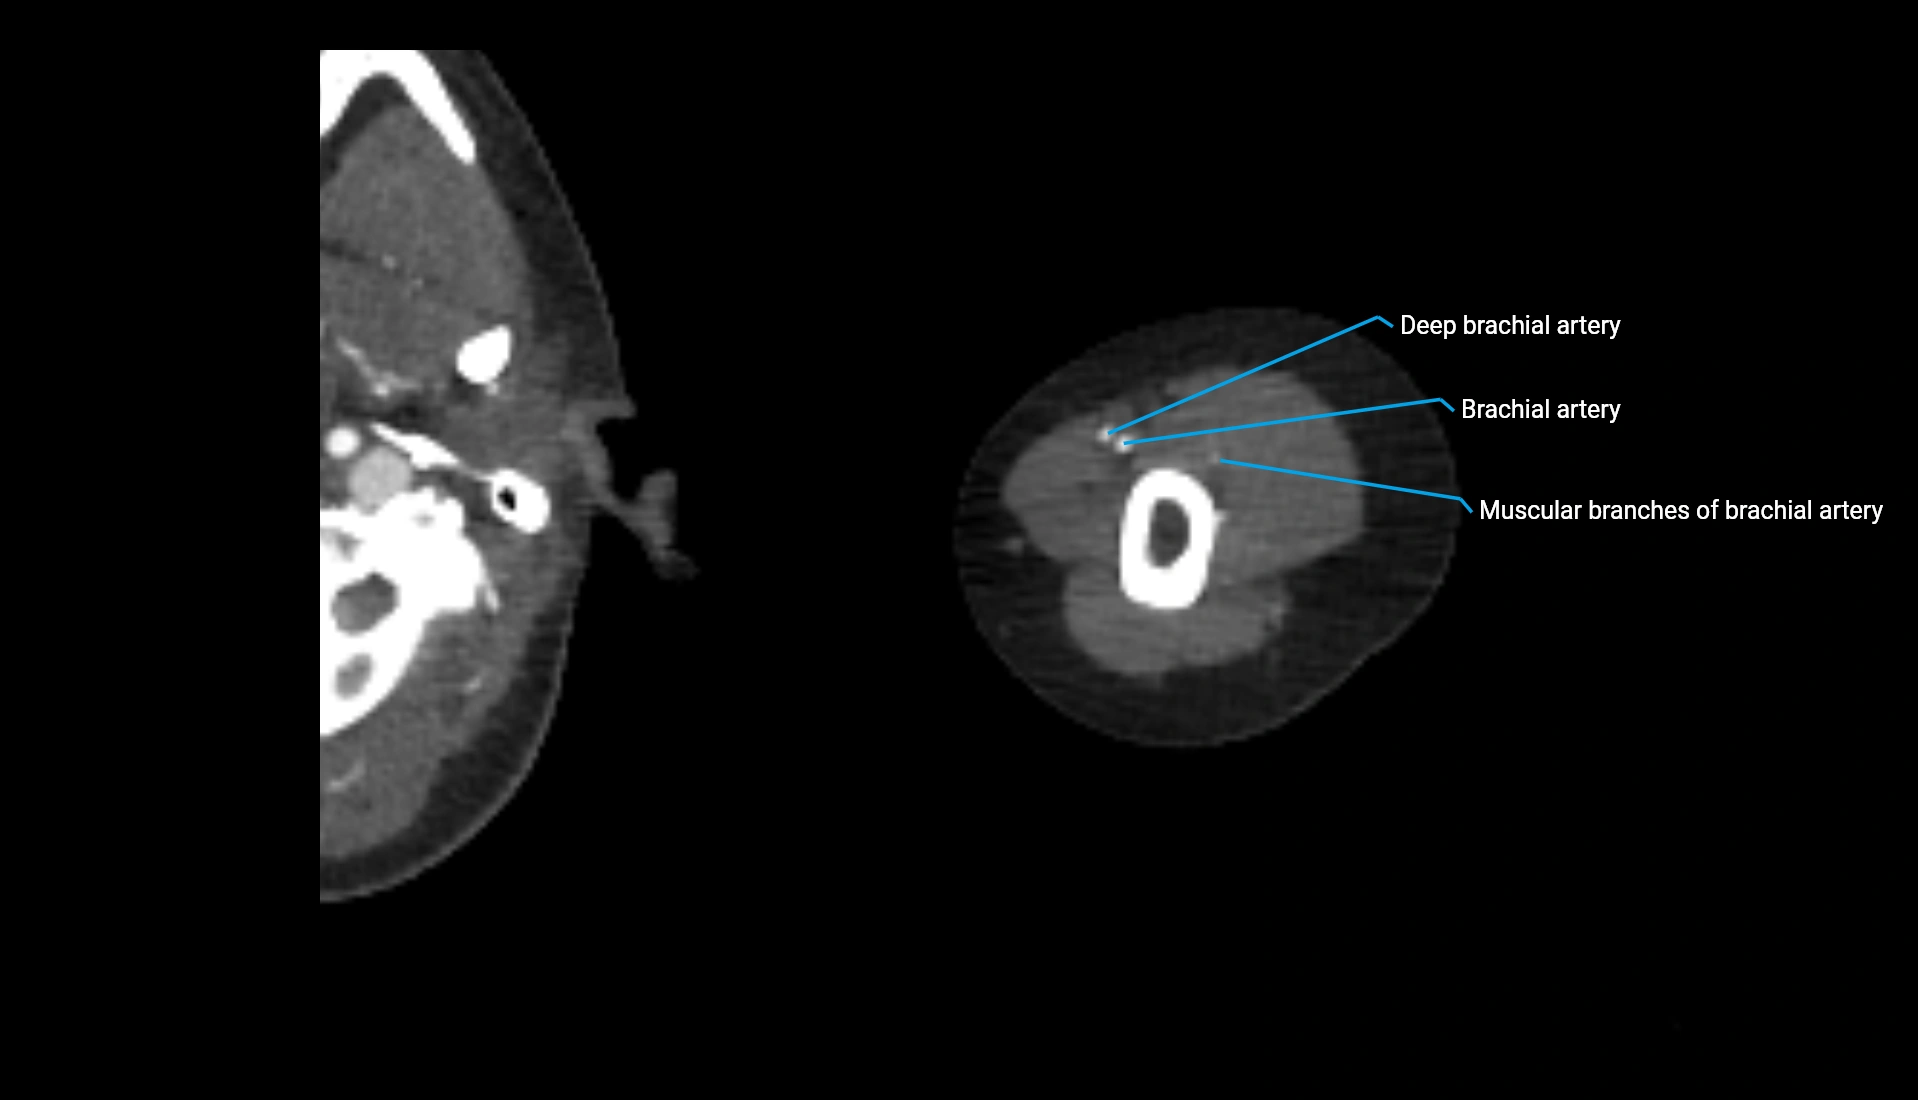

CT Appearance

Non-Contrast CT:

• Cortex: High-density, sharply defined

• Subchondral bone: Dense cancellous matrix

• Articular surface: Smooth concave contour articulating with the capitellum

• Excellent for evaluating bone integrity, alignment, and subtle fractures